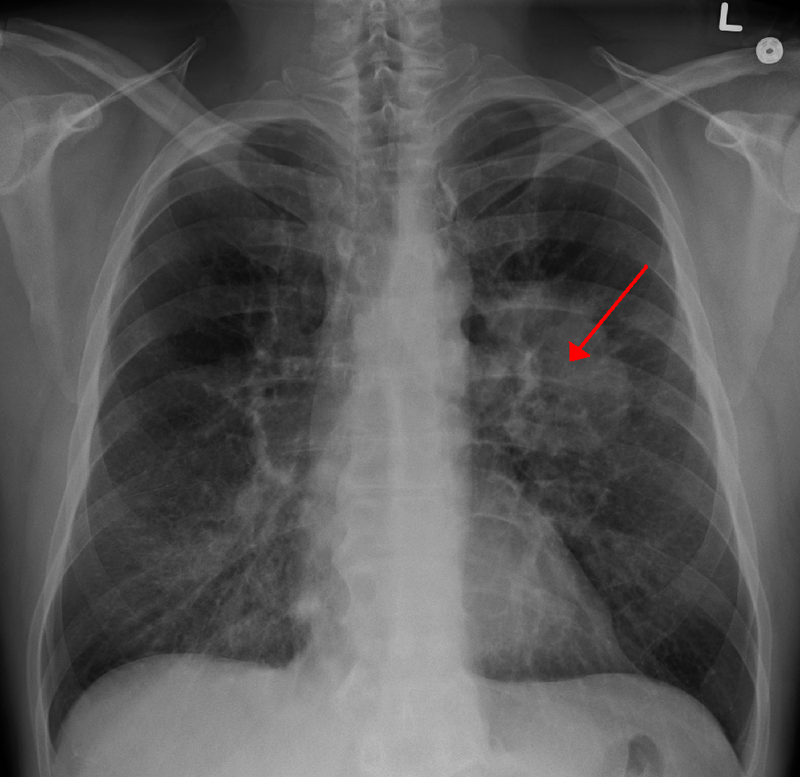

În 2022, cancerul pulmonar era cea mai frecventă formă în întreaga lume (2,5 mil. cazuri). Numărul cazurilor de cancer va crește cu 77% până în 2050. Este anunțul alarmant din partea Organzației Mondiale a Sănătății.